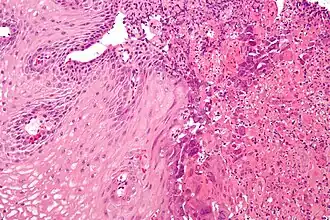

Coupe histologique de l’œsophagite.